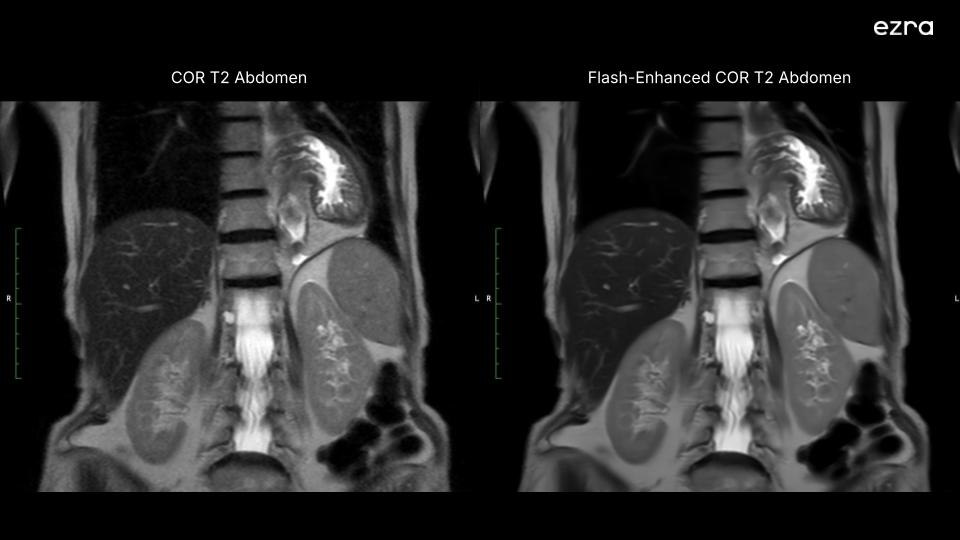

I'm excited to share that Ezra has received new FDA 510(k) clearance for a new version of our Ezra Flash AI. This clearance significantly expands our ability to enhance MR image quality, including the abdomen and pelvis, building upon our previous neuro imaging capabilities.

First, our Ezra Flash AI now delivers improved image quality by effectively reducing noise while preserving crucial diagnostic information across neuro, abdomen, and pelvis. This enhancement is particularly important for complex anatomical areas like the abdomen and pelvis, where clear imaging is essential for accurate screening.